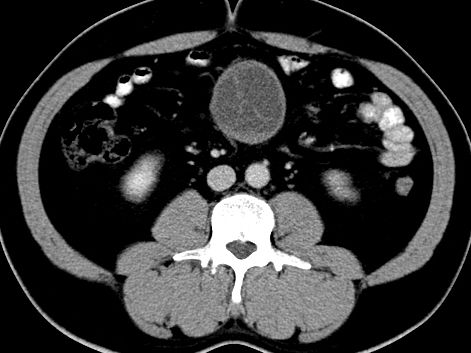

(腹腔)神经鞘瘤

男,48岁,间断性下腹不适1年。

手术探查

:距回盲部28厘米处肠系膜根部可见5*7cm左右包块,质中等硬度,活动度尚可,肝、胆、胰、脾肾未见明显异常。

病理

:(腹腔)

神经鞘瘤

,伴出血、坏死及囊性变,伴淋巴结反应性增生。

免疫组化结果

:sma(-), desmin(-), cd117(-), s-100(+++), nf(-),vimentin(+++).